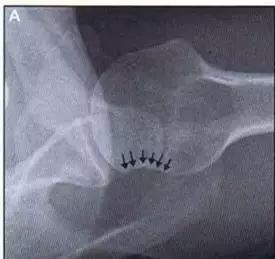

11. Shepherd 骨折

距骨后结节的骨折。

(来源:Talar process or tubercle [Shepherd’s fracture)

12. Cedell 骨折

距骨后内侧结节骨折。

Cedell 骨折的 CT 片 (来源:Fracture of the posterior medial tubercle of the talus :A case report and review of the literature. Acta Orthop. Belg., 2007, 73, 804-806)